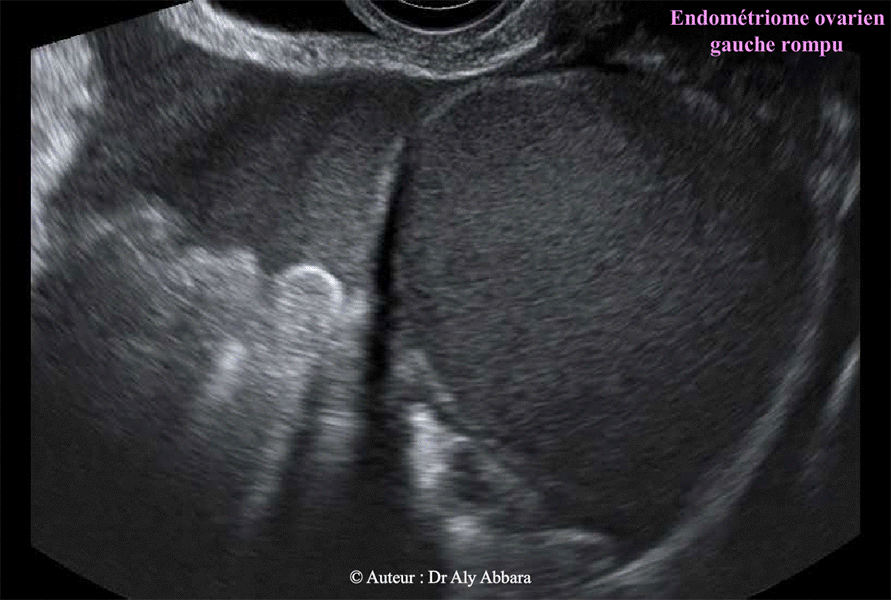

• Images échographiques montrant l'aspect ultra-sonore d'un endométriome (kyste endométriosique) ovarien gauche de 128 cm3 de volume.

Il s'agit d'une formation kystique uniloculaire mesurant (6

6 x 64 x 58 mm) ; à paroi régulière, de 1 à 2 mm d'épaisseur, sans végétation endophytique.

Le contenu du kyste est liquidien, homogène

, hypo-échogène correspondant cliniquement à un liquide formé du sang lysé, concentré et épaissi, prenant un aspect chocolatoïde (comme le chocolat fondu), qu'on voit normalement dans les kystes endométriosiques (endométriomes).

L'exploration opératoire, et l'examen anatomopathologique confirment la nature histologique de ce kyste ; il s'agit d'un endométriome ovarien gauche rompu, isolé (kyste d'endométriose), sans aucune d'autre lésion abdomino-pelvienne ou péritonéale individualisable associée et sans phénomènes adhérentiels i

ntra-abdominal.